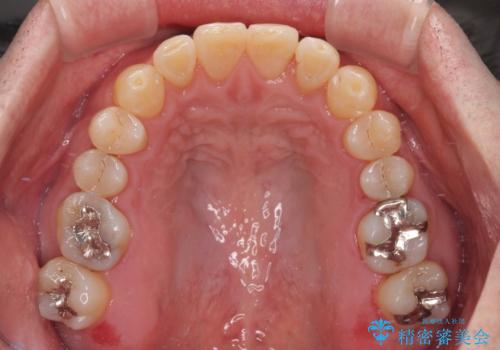

受け口を治す ワイヤー装置での矯正治療

歯並びや口元の印象、奥歯の咬み合わせから、非抜歯にて矯正治療を行うこととしました。

インプラント埋入による仮歯の装着や、前歯の反対咬合の改善は比較的スムーズに達成されましたが、舌突出癖などの影響による、歯列全体のスペースを閉じることが難航し、期間がかかってしまいました。